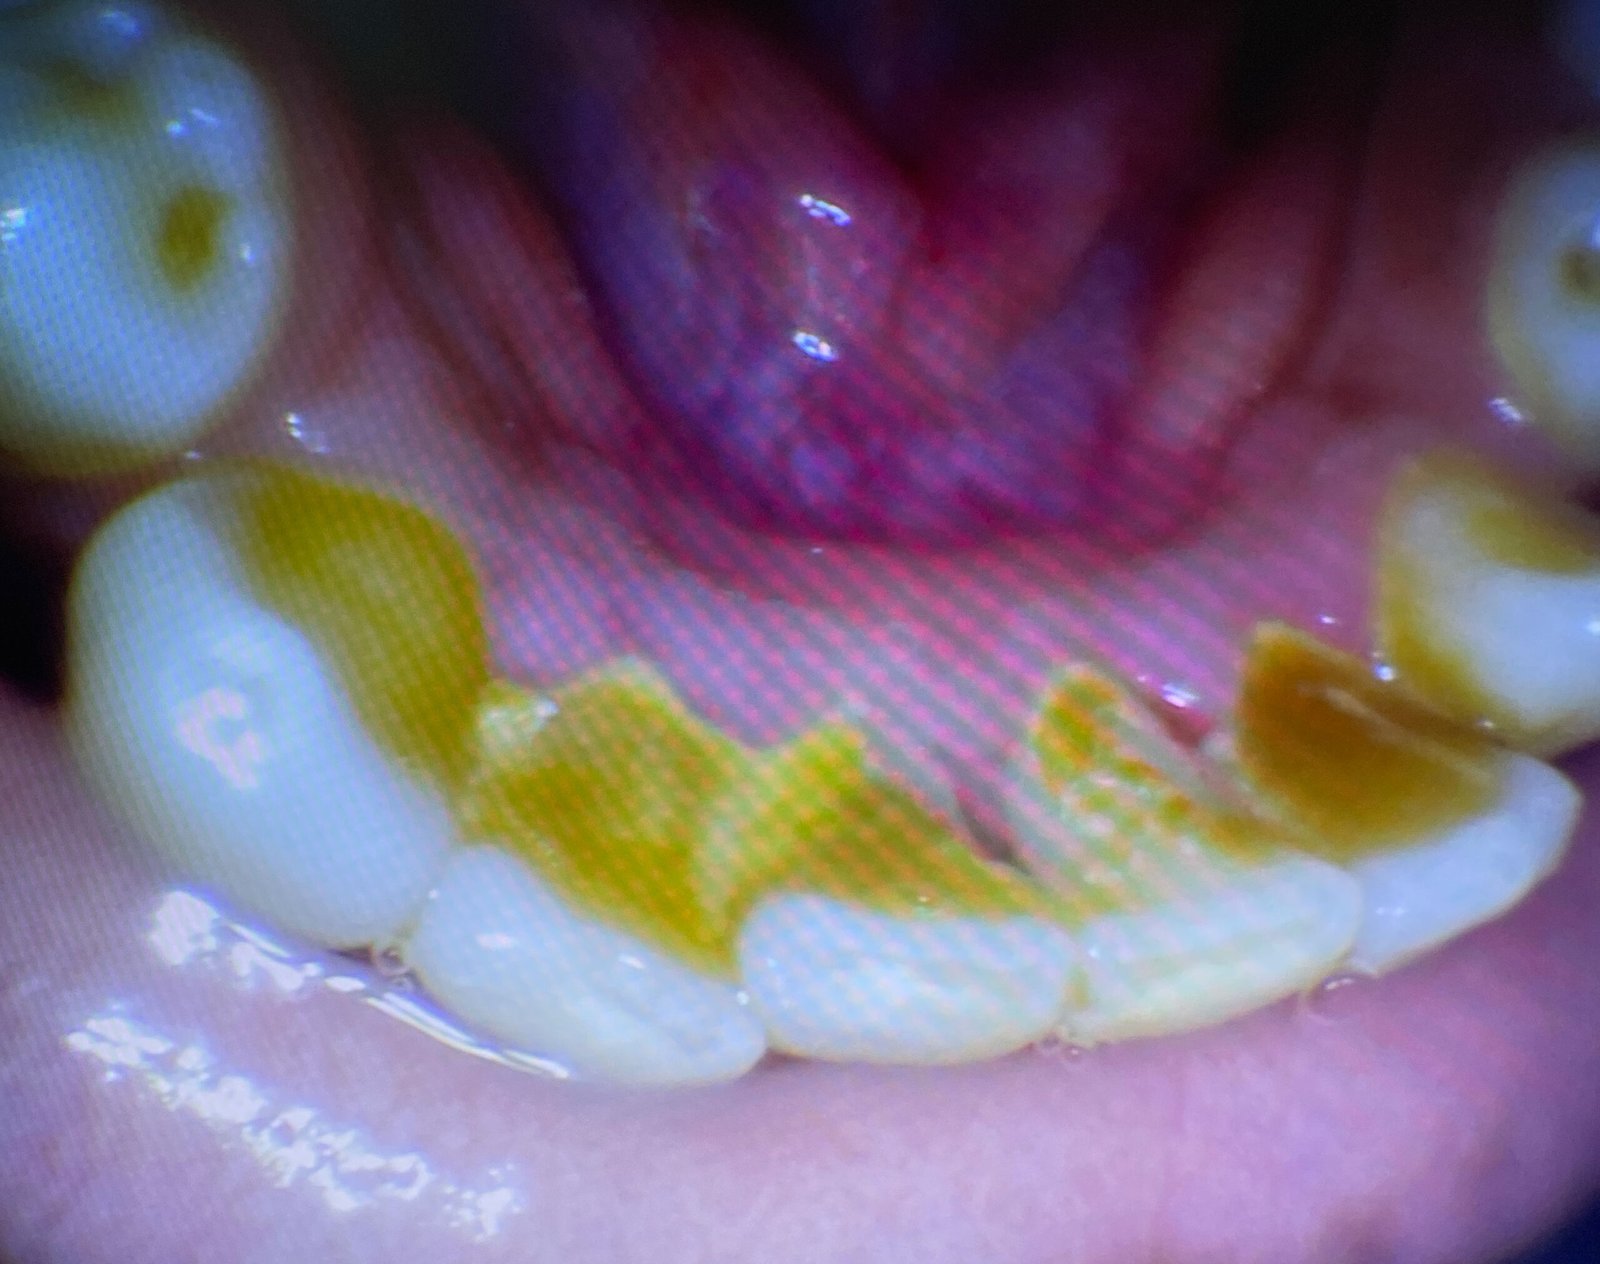

Following scaling, dental polishing is done to smoothen the tooth surfaces and remove any residual stains caused by tea, coffee, smoking, or certain foods. A soft rubber cup and a special polishing paste are used to give your teeth a smooth and shiny finish. Polishing not only enhances your smile aesthetically but also makes it harder for plaque to accumulate on clean surfaces.